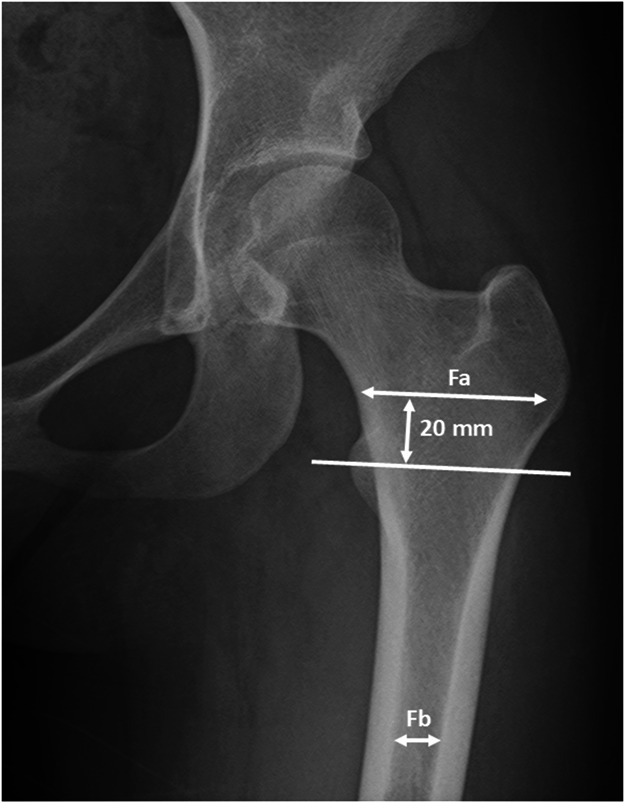

背景:术中骨折是老年髋部骨折双相半关节置换术的重要并发症。股骨几何形状为Dorr C与术中骨折的高风险相关。然而,从受伤到手术的持续时间对术中骨折风险的影响尚不清楚。我们假设从受伤到手术的时间延长会增加术中骨折的可能性。本研究的目的是评估从损伤到手术的时间与术中骨折的发生之间的关系。方法:本病例对照研究分析了2017年4月至2024年3月在2家医院接受双相半关节置换术治疗髋部骨折的548例患者。根据术中骨折的发生情况将患者分为“术中骨折(+)组”和“术中骨折(-)组”。评估术中骨折与损伤至手术时间的关系。结果:548例患者中37例发生术中骨折。术中骨折(+)组和(-)组损伤至手术时间分别为6.05天和3.56天(p = 0.002)。术中骨折(+)组和(-)组的椎管闪耀指数(CFI)分别为3.30和3.73 (p < 0.001)。Logistic回归分析显示,损伤至手术时间的回归系数为0.04 (p = 0.04), CFI的回归系数为-1.09 (p < 0.001),均与术中骨折风险增加相关。在术中骨折患者中,一项对手术延误超过48小时的调查显示,这些延误中有一半以上是由于医院相关的问题。结论:术中骨折随CFI和损伤至手术时间的延长而增加。在某些情况下,医疗设施可能能够缩短这一持续时间。为了尽量减少老年患者双相半关节置换术中骨折的风险,减少从损伤到手术的持续时间至关重要。证据等级:III级,病例对照研究。有关证据水平的完整描述,请参见作者说明。

Results: Intraoperative fractures occurred in 37 of 548 cases. The duration from injury to surgery was 6.05 and 3.56 days in the intraoperative fracture (+) and (-) groups, respectively (p = 0.002). The canal flare index (CFI) was 3.30 and 3.73 in the intraoperative fracture (+) and (-) groups, respectively (p < 0.001). Logistic regression analysis revealed that the regression coefficient for the duration from injury to surgery was 0.04 (p = 0.04), and for CFI -1.09 (p < 0.001), both associated with an increased risk of intraoperative fracture. In patients with intraoperative fractures, an investigation into delays in surgery beyond 48 hours showed that more than half of these delays were due to hospital-related concerns.